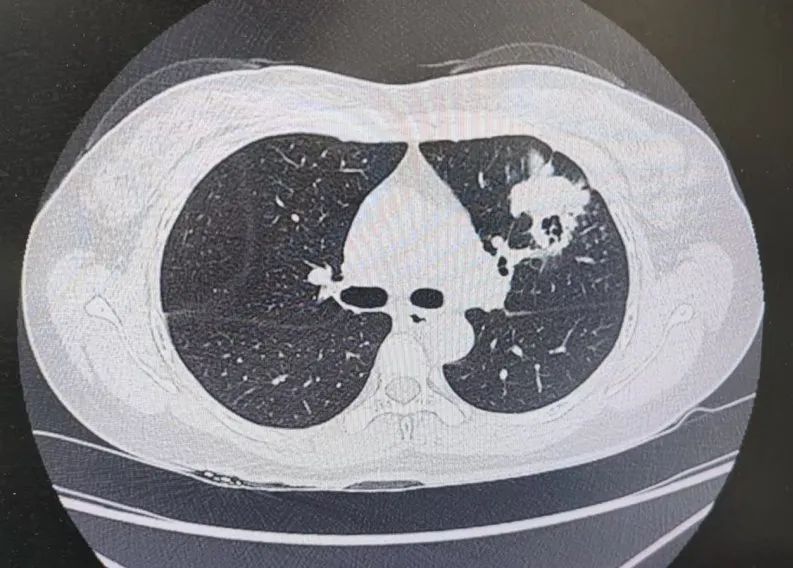

患者肺部CT影像

“一般来说,肺炎经过一周的抗感染治疗,病灶会有所吸收。但陈女士的肺部阴影纹丝不动,这种情况必须提高警惕。”宋刚主任团队立即启动了更深入的“三部精准诊断”程序:

1、支气管镜探查:快速排除气道新生物;

2、肿瘤标志物追踪:多项血清指标显著升高,直指肿瘤可能;

3、CT引导下穿刺活检:病理诊断为左肺上叶腺癌。

肺炎型肺癌,因其影像学表现与普通肺炎极为相似,临床上误诊率极高。然而确诊仅是第一步。宋刚主任当天即召集肿瘤科、病理科、影像科等多学科专家会诊,为陈女士制定个体化治疗方案。